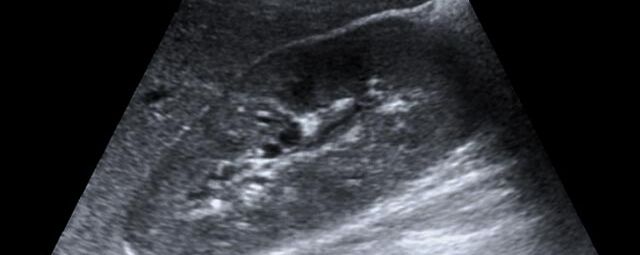

Die Sonographie ist ein bildgebendes Verfahren in der medizinischen Diagnostik, das mit Ultraschallwellen arbeitet. Ultraschall ist Schall mit einer Frequenz oberhalb der menschlichen Hörgrenze. Im medizinischen Bereich werden je nach Körperregion Ultraschallwellen in einem Frequenzbereich von ca. 3,5 – 18 Mhz verwendet. Die körpernahe Ultraschallsonde sendet durch einen piezoelektrischen Effekt kurze Schallwellenimpulse in den Körper. Ultraschall-Gel stellt den Kontakt zwischen Sonde und Körper her. Je nach Gewebeart werden diese Schallwellen im Körper unterschiedlich stark reflektiert. Anhand des zurückgesendeten Schallmusters kann das Ultraschallgerät Schnittbilder berechnen, auf denen die Organe des Körpers nach krankhaften Veränderungen untersucht werden können.